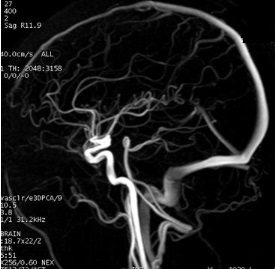

Inhance: 3D Velocity scan

Use Inhance 3D Velocity to acquire contrast-free angiography images with excellent background suppression at a shorter scan time in comparison to 3D PC. Typically used for renal and brain scans.

- Scan plane: For brain scans, select a sagittal scan plane to reduce the number of slices and thus the scan time. For renal scans, select an axial plane.

- Deposit a sagittal slab for brain scans.